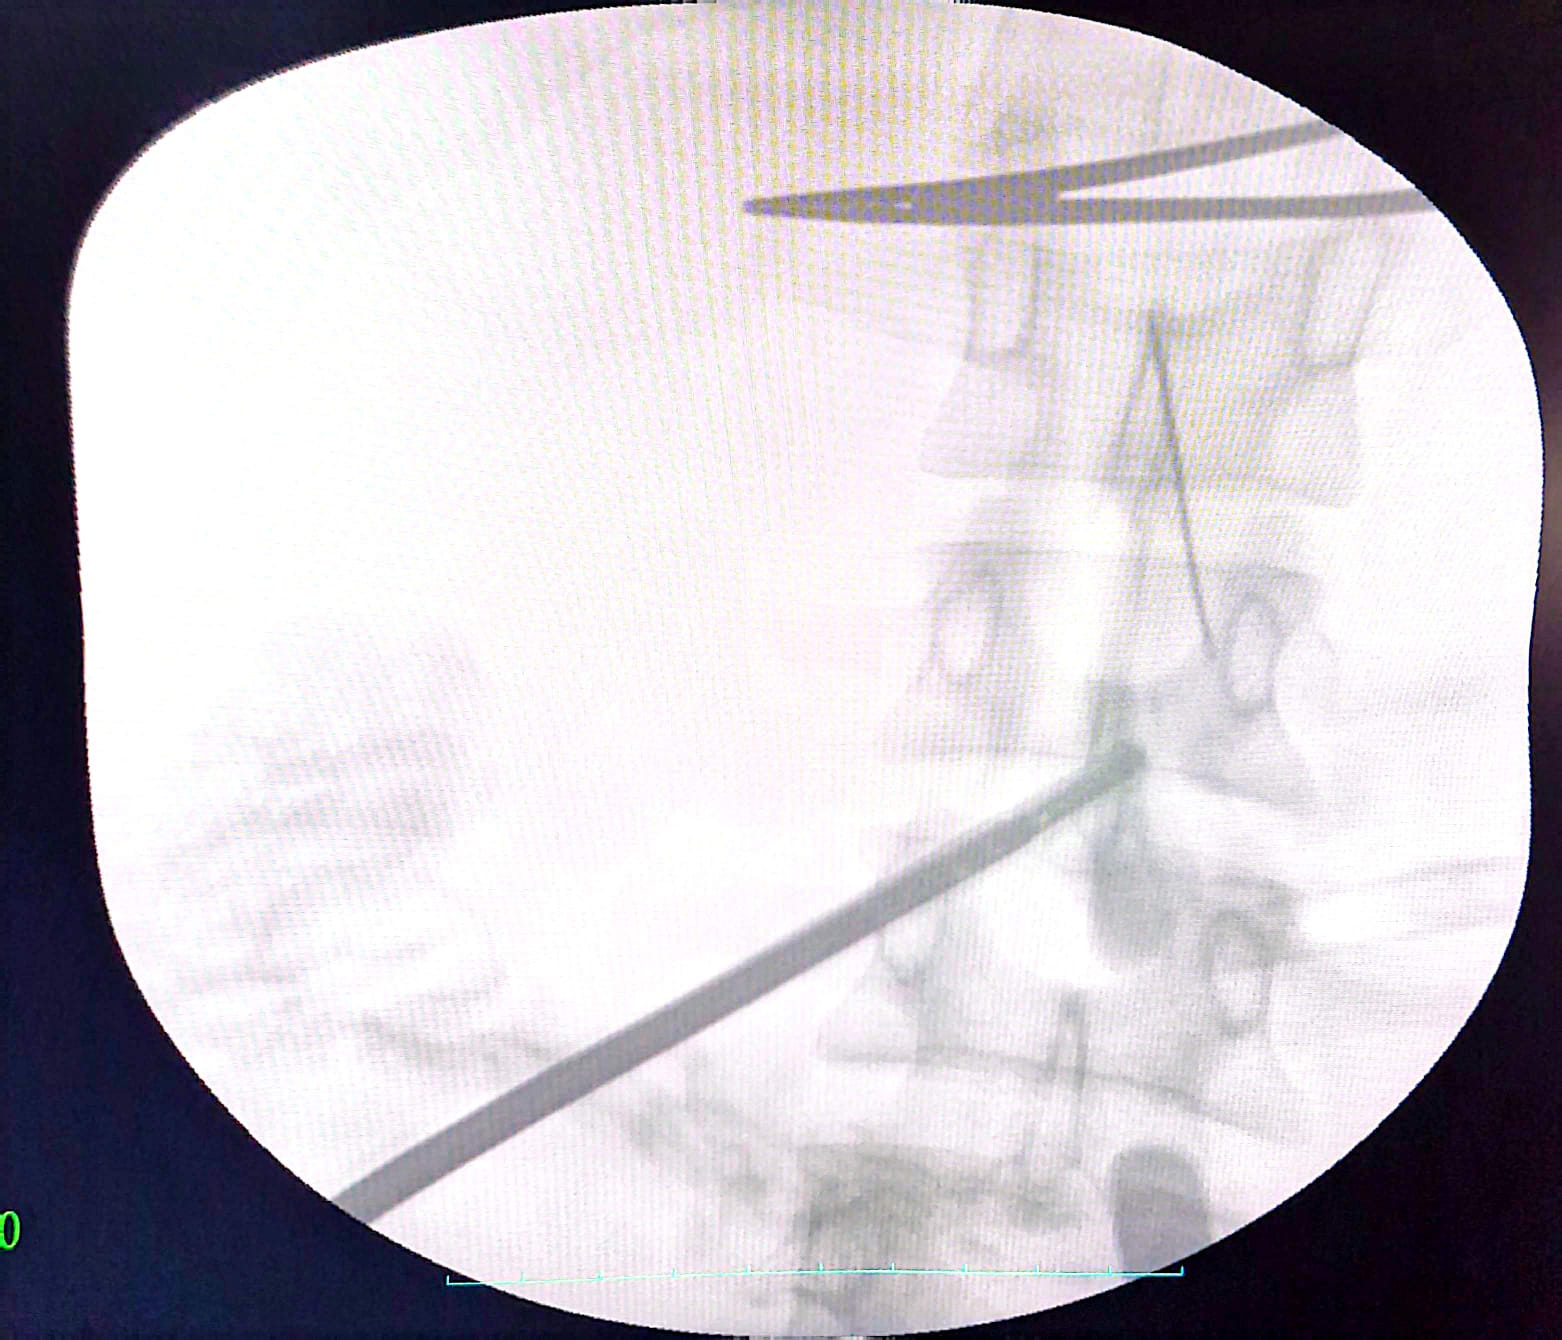

وأجرى الفريق الطبي العملية باستخدام المنظار عبر 3 فتحات صغيرة، مع الاستعانة بجهاز الأشعة (C-Arm) لتحديد موقع الإبرة بدقة، بدلاً من الجراحة التقليدية (فتح البطن)، ما ساهم في تقليل التدخل الجراحي وتسريع التعافي.